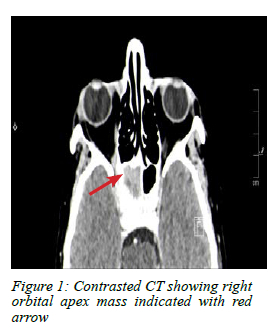

A computed tomography (CT) scan of the brain and paranasal sinuses showed a mass lesion in the right parasellar region and orbital apex with extension into the sphenoid sinus (Figure 1 and 2).

The diagnostic algorithm includes a full physical examination and imaging. CT scan of the brain and paranasal sinus is the primary imaging modality of choice as it can demonstrate a mass in the orbit. Magnetic resonance imaging (MRI) scans help delineate the mass from the surrounding soft tissue structures.2-49 In our patient, MRI was not performed as the CT scan clearly delineated the pathology and site.

Blindness and ophthalmoplegia from breast cancer metastases to the orbital apex and sphenoid sinus after a 10-year disease-free interval is very rare. Involvement of the optic nerve differentiates this presentation from other forms of ophthalmoplegia found in the superior orbital fissure and cavernous sinus syndrome. A high-resolution CT scan is often sufficient to delineate the location and extent of the disease, and guide biopsy which is necessary to determine the aetiology and origin of the disease. A PET scan is used for oncological staging and to guide appropriate treatment. Prognosis for orbital metastasis of breast cancer is poor with an average survival of 31 months.4